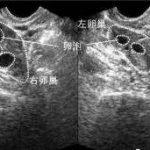

第三代试管婴儿技术是在传统试管婴儿技术基础上进一步发展而来的。它采用了PGS/PGD(胚胎植入前遗传学诊断)技术,可以检测出胚胎染色体异常和单基因遗传病,并选择健康的胚胎进行移植。

1.检测基因疾病:通过PGS/PGD技术,可以精准地检测出胚胎是否携带有基因疾病的遗传物质。